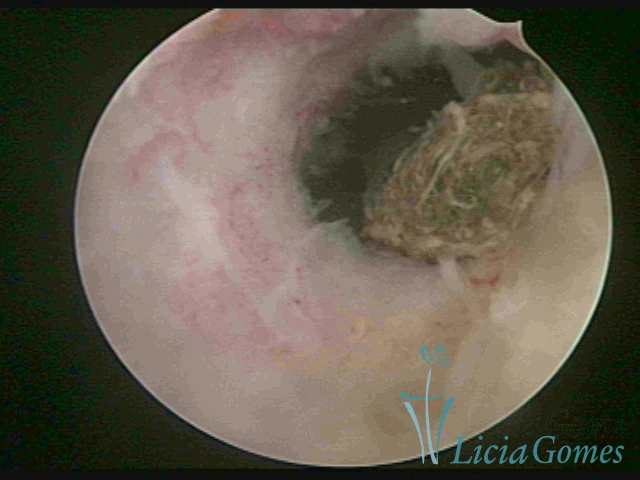

Uterine cavity with a fragmented IUD debris, inserted 46 years ago.

×